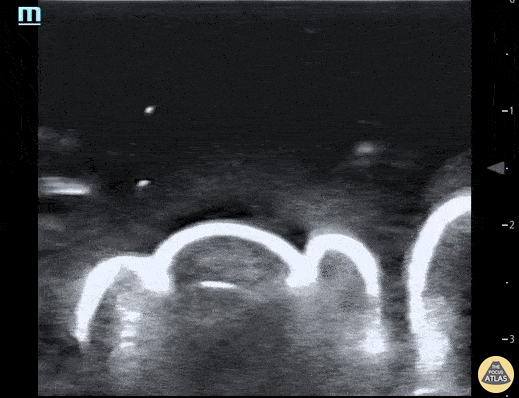

Pictured here is a water bath scan using a high frequency linear transducer; specifically this image visualizes the distal right great toe of a healthy young adult. Water bath scanning is a technique that augments the clarity and distinctness of structures that are otherwise challenging to visualize with POCUS including distal digital examinations. In addition to yielding higher quality images, the use of a water bath circumvents the need for direct contact with the area of interest, often resulting in less patient discomfort. Moudi Hubeishy, MD. Rural Medicine PGY1. California, USA @Hubeishy_MD